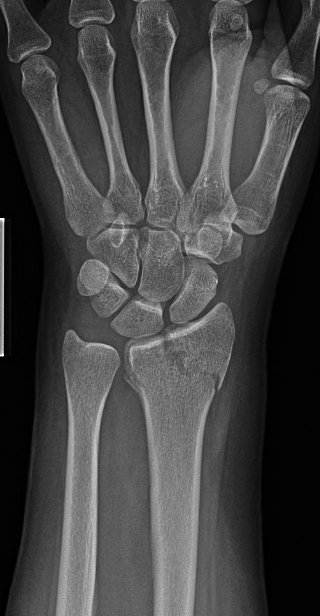

24y/o healthy RHD F who works in an office job fell roller skating.

Nothing surprising on exam

Given frx pattern and risk for concomitant SL injury (and ?SL widening), started scratching the ole’ noggin.

Couldn’t do dynamic (grip) view for injured side so we went for a contralateral comparison. Subtle differences if any…